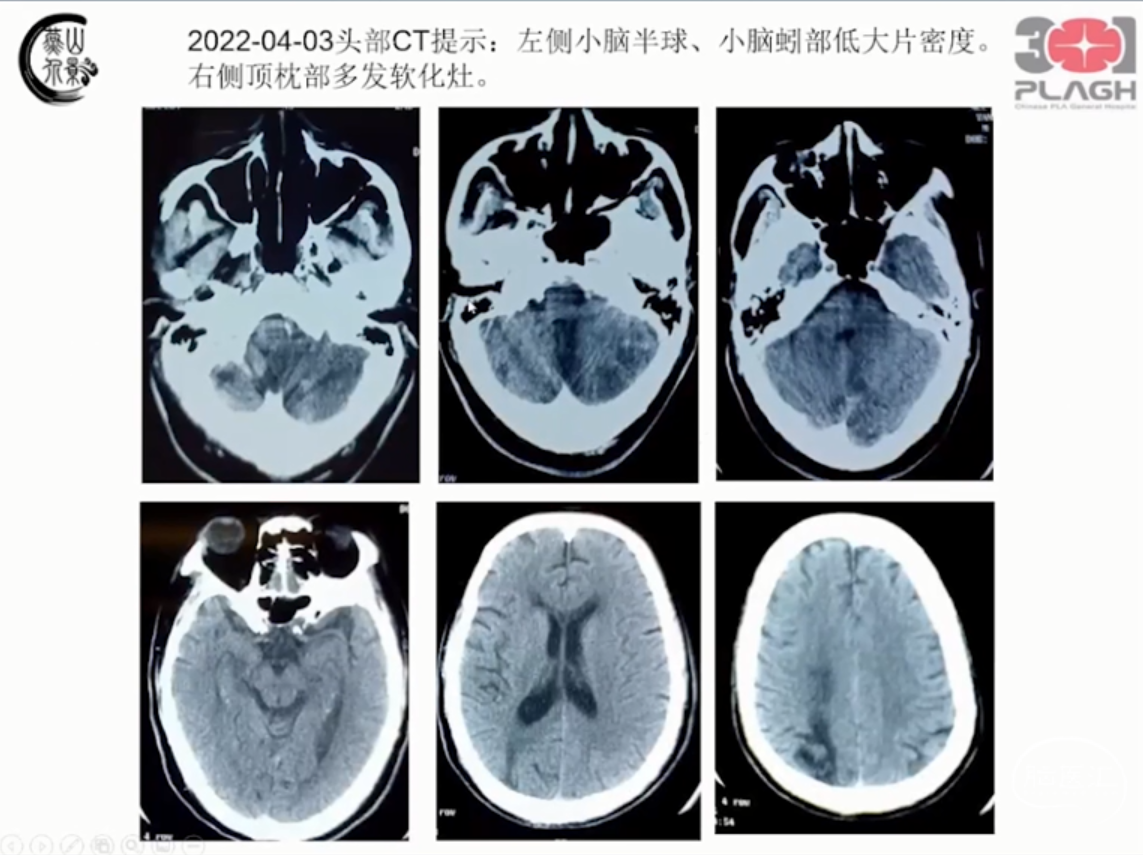

左侧椎动脉V4段重度狭窄支架置入术

解放军总医院第一医学中心 王君教授团队